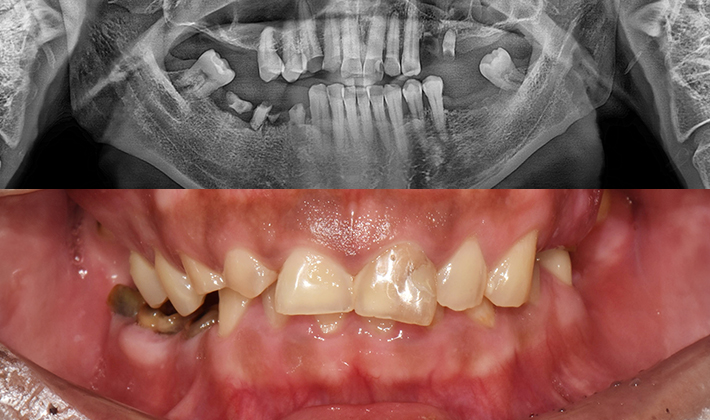

치과가 무서워 10년 동안 미뤄온 임플란트 수술 그 결과는?

2026.01.21